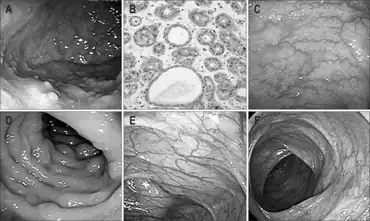

| a) Multiple fundic gland polyps b)dilated oxyntic glands c,d) multiple colonic polyps e,f) diminished colonic polyps at 1 year | |

Attenuated familial adenomatous polyposis is a form of familial adenomatous polyposis, a cancer syndrome. It is a pre-malignant disease that can develop into colorectal cancer. A patient will have fewer than a hundred polyps located typically in right side of the colon. Cancer might develop as early as the age of five, though typically presents later than classical FAP.[1]